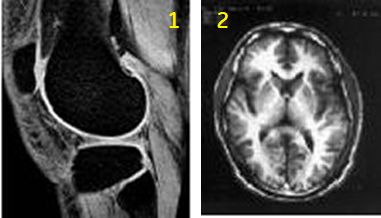

Use IR sequences to produce T1-weighted or fat-suppressed images, particularly in abdomen or extremities.

| Number | Description |

|---|---|

| 1 | IR knee image |

| 2 | IR brain image |

Consider this information when modifying Inversion Recovery scan parameters. For specific scan parameter values, select a protocol from your GE or Site library.